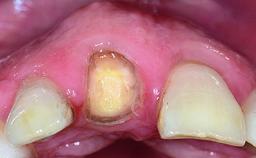

A 32-year-old female Caucasian patient with a compromised maxillary right central incisor was referred to us by a general dentist. Her chief complaints were discomfort and mobility of tooth 11 with unsatisfactory esthetics due to discoloration. The patient reported a previous trauma, some years earlier, as the origin of pathology on the afflicted tooth. Anamnesis was negative for any other dental or periodontal pathology in the remaining dentition. The patient did not take any medication and reported to be a light smoker (5–10 cigs/day). She had high esthetic expectations of her treatment. The extraoral examination revealed a high smile line with full exposure of her maxillary teeth and surrounding soft tissue in the area between the second premolars.

Soft Tissue Anatomy Intact Defective

Bone Volume Horizontally and vertically sufficient Horizontally deficient Deficient vertically or deficient vertically AND horizontally

Soft Tissue Contour and Volume Slightly compromised